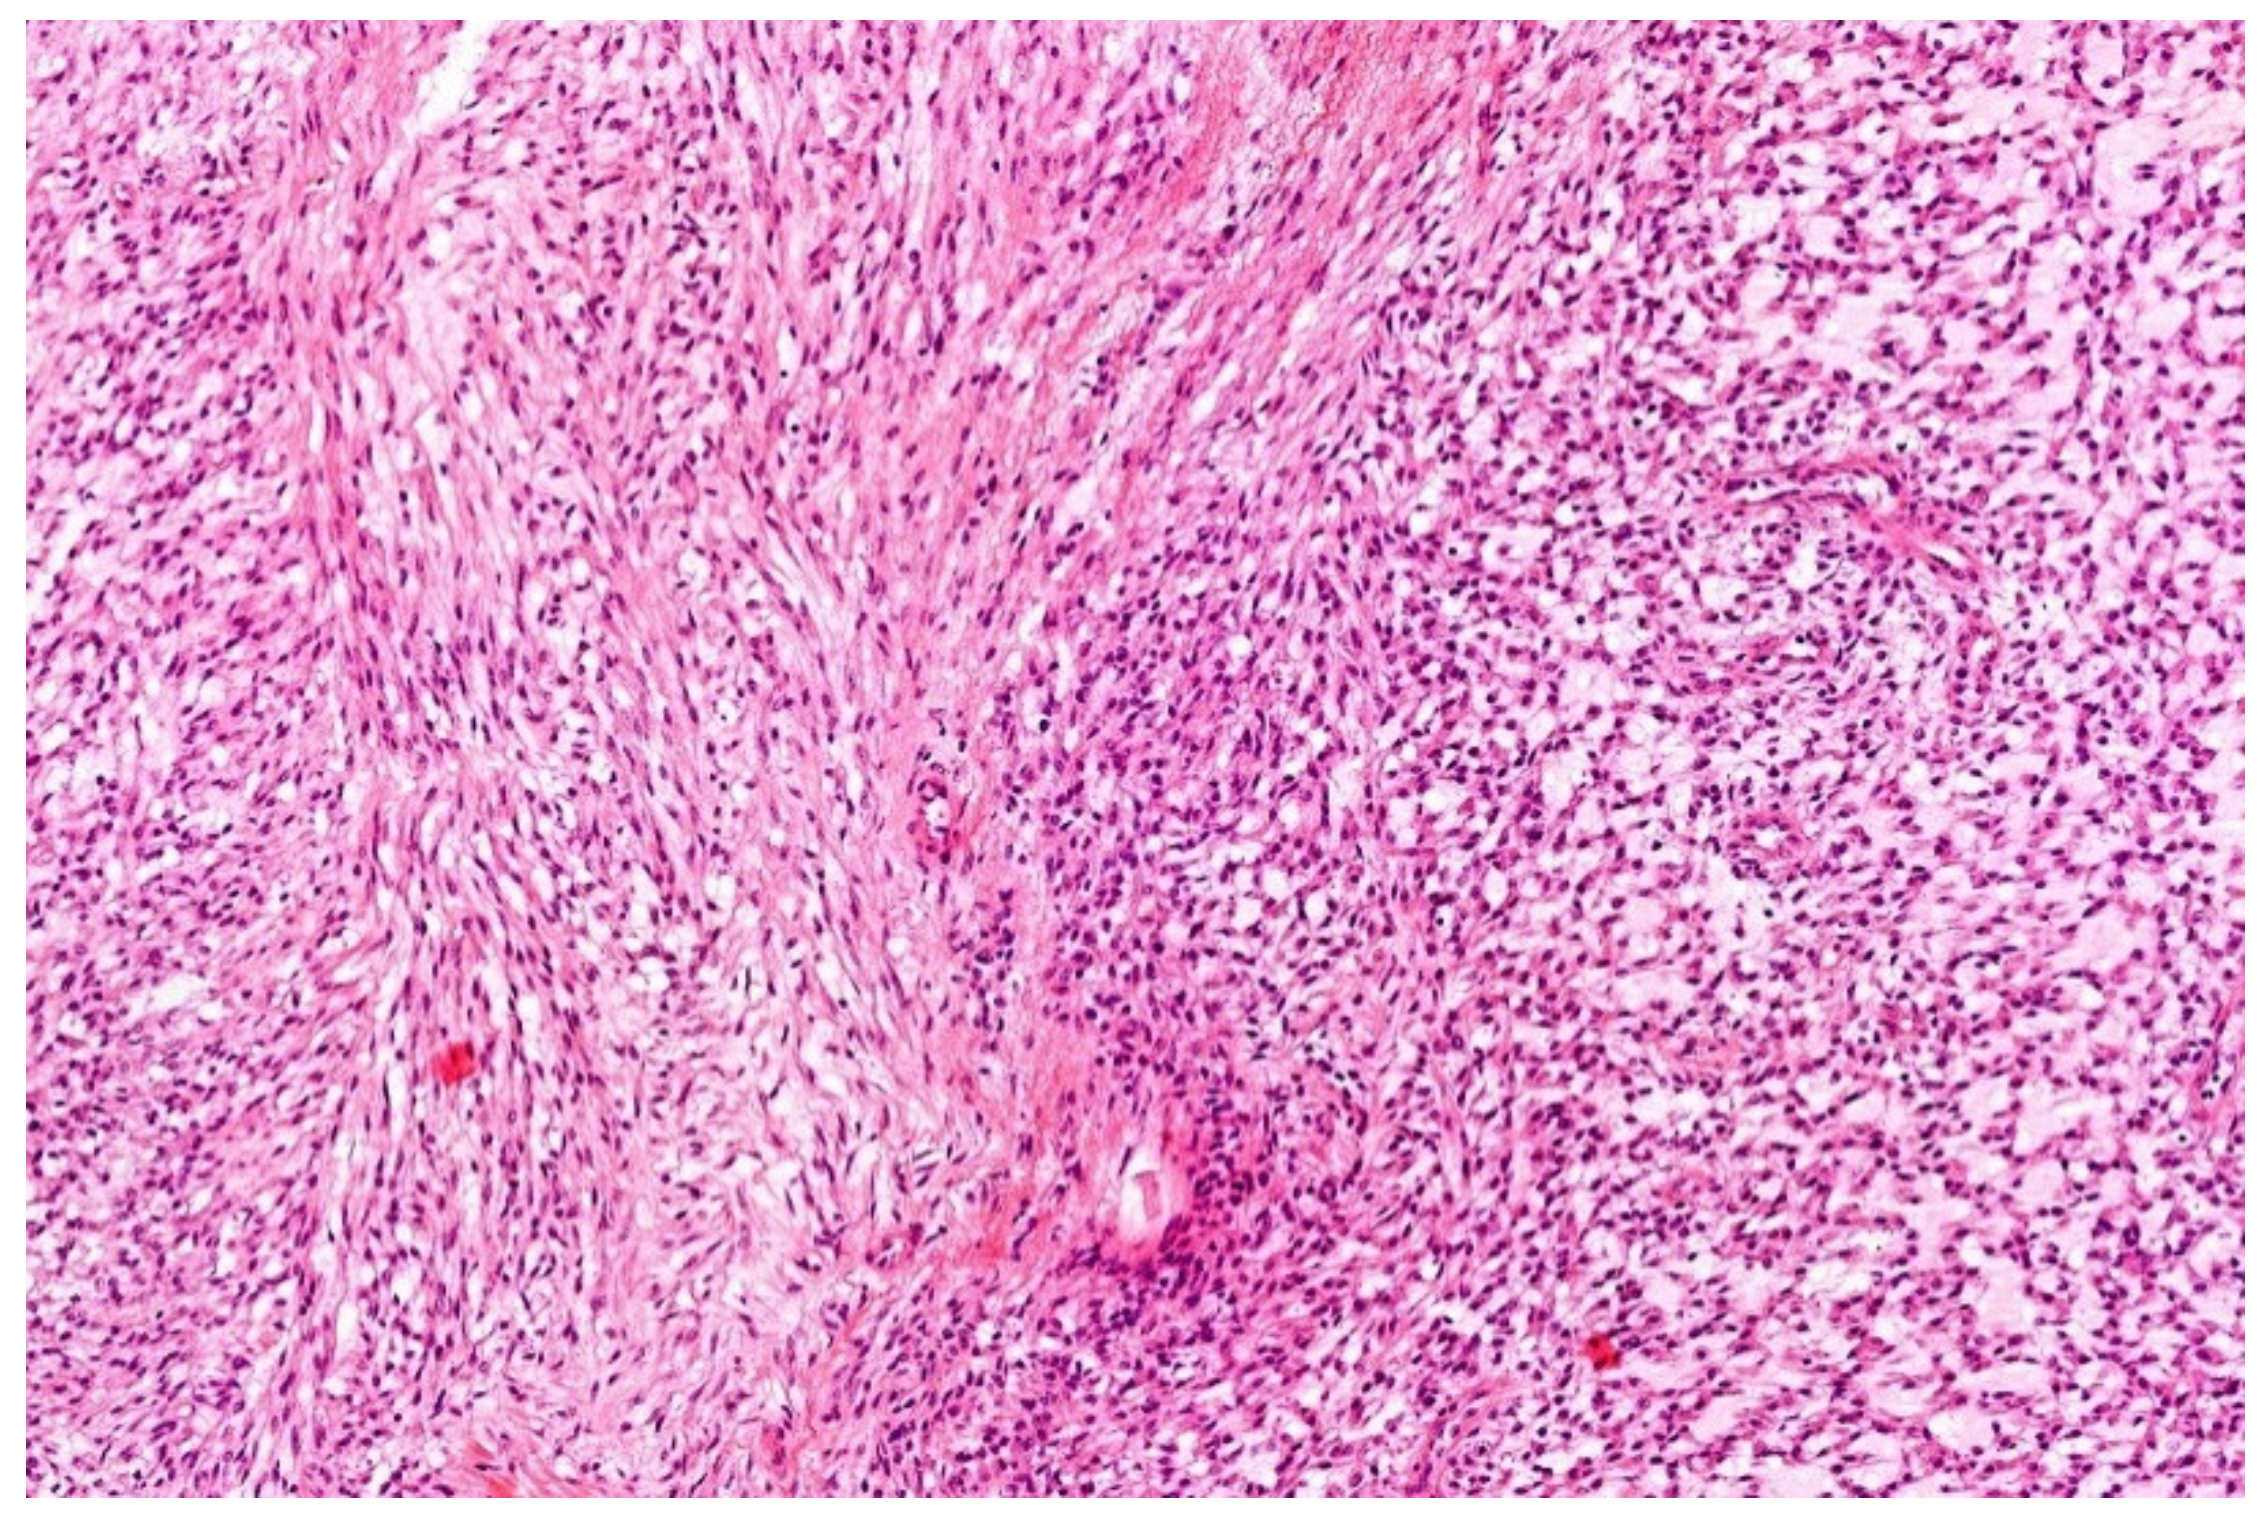

- Low-grade appearing tumors: the spindled, epithelioid, ovoid, and round cells are set in a hyaline stroma reminiscent of solitary fibrous tumors and myoepithelioma.

- Intermediate and high-grade appearing neoplasms have a round and/or ovoid morphology with few spindle cells and slight stromal component. The tumors of this second subgroup resemble other small, blue round-cell tumors, e.g., ARMS, BCOR-, and CIC-rearranged sarcoma.